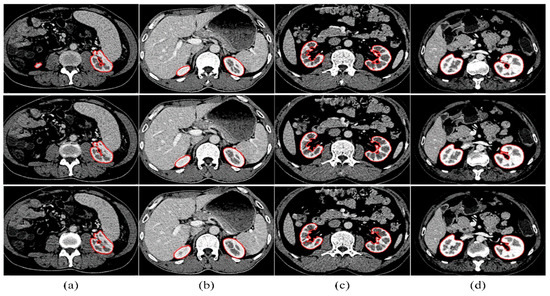

Kidney segmentation from abdominal computed tomography (CT) images is essential for computer-aided kidney diagnosis, pathology detection, and surgical planning. This paper introduces a kidney segmentation method for clinical contrast-enhanced CT images. First, it begins with shape-based preprocessing to remove the spine and ribs. [...] Read more.

Kidney segmentation from abdominal computed tomography (CT) images is essential for computer-aided kidney diagnosis, pathology detection, and surgical planning. This paper introduces a kidney segmentation method for clinical contrast-enhanced CT images. First, it begins with shape-based preprocessing to remove the spine and ribs. Second, a novel clustering algorithm and an initial kidney selection strategy are utilized to locate the initial slices and contours. Finally, an adaptive narrow-band approach based on active contours is developed, followed by a clustering postprocessing to address issues with concave parts. Experimental results demonstrate the high segmentation performance of the proposed method, achieving a Dice Similarity Coefficient of 97.4 ± 1.0% and an Average Symmetric Surface Distance of 0.5 ± 0.2 mm across twenty sequences. Notably, this method eliminates the need for manually setting initial contours and can handle intensity inhomogeneity and varying kidney shapes without extensive training or statistical modeling. Full article